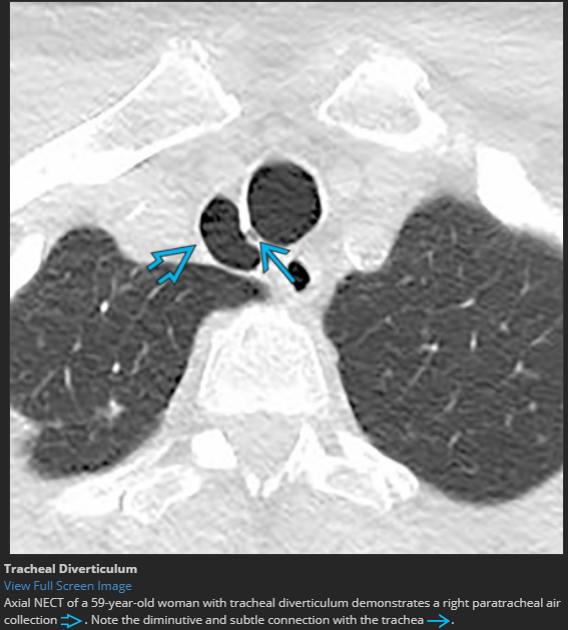

asymptomatic patient

tracheal diverticulum